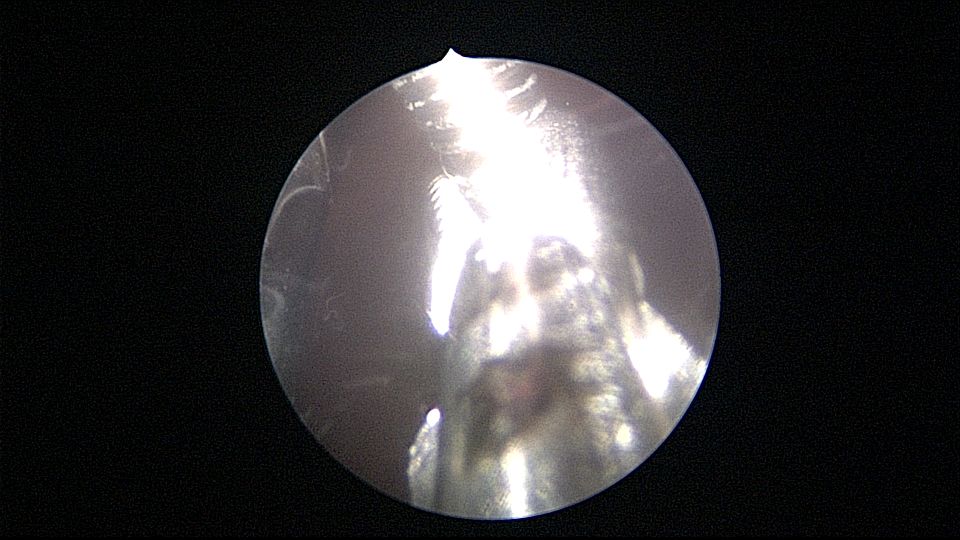

患者55岁,G5P1,顺产1次。安环20年,绝经8年。子宫后位,外阴、阴道及宫颈萎缩,宫深6.5cm,宫颈内口封闭粘连,镜鞘推开粘连,见灰白色脓液,O型环位置正常,异物钳顺利取出节育环,膨宫液冲洗脓液,宫腔无其他异常。